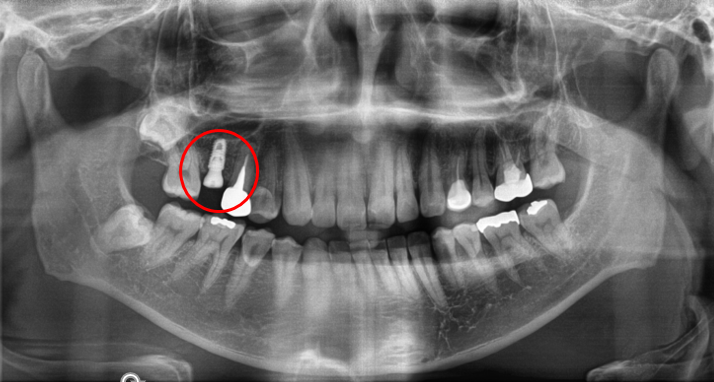

2단계는 '픽스처'로 치아 기둥을 식립합니다.

단단한 지지대 역할을 하는 픽스처는 잇몸 속 턱뼈 안에 심게 됩니다. 자연치아처럼 '단단히 고정'될 수 있도록 치아의 기둥 역할을 해줍니다.

청담역치과 2021-07-27 픽스처 심은 모습

잇몸 안에서 픽스처가 자리 잡는 데는 시간이 필요합니다.